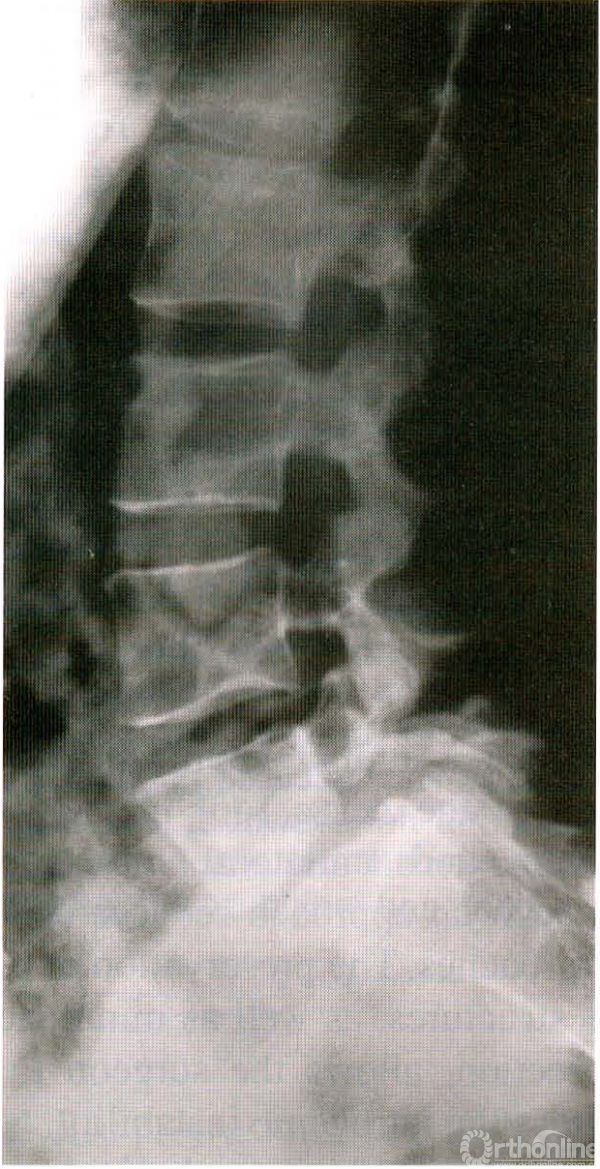

而那些具有双侧下肢症状、中到重度腰背痛和/或屈曲位X片上滑脱加重的患者,不能只进行单侧显微减压手术。适合该术式的X线片(见图5)。该手术的优点:切口小、手术时间短、不需要植骨及内固定,可明显减少手术的并发症;重要的是该手术不需要同时进行椎间盘摘除术,因为后者可能会增加术后脊柱不稳定,促进术后滑移发展和腰背部疼痛;术中对骨质的切除及软组织的剥离降到最低,医源性脊柱不稳的风险也随之大大减小。

图5 稳定性L5-S1峡部裂性腰椎滑脱的患者,主要表现为放射性疼痛、无腰背痛、屈曲-伸展X片无移位。